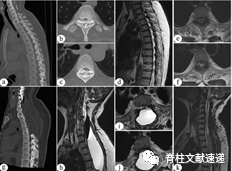

图注:一名PMC患者接受保守治疗。a-f术前CT和MRI显示C7-T3 OPLL和T2-4 OLF。g 在C7–T5进行椎板切除减压,在T1–2进行环形减压。h–j 初次手术后21天发现切口肿胀,MRI显示巨大PMC形成。患者接受保守治疗(卧床休息、局部压迫和超声引导穿刺)。K 保守治疗后3个月的MRI显示PMC完全吸收。